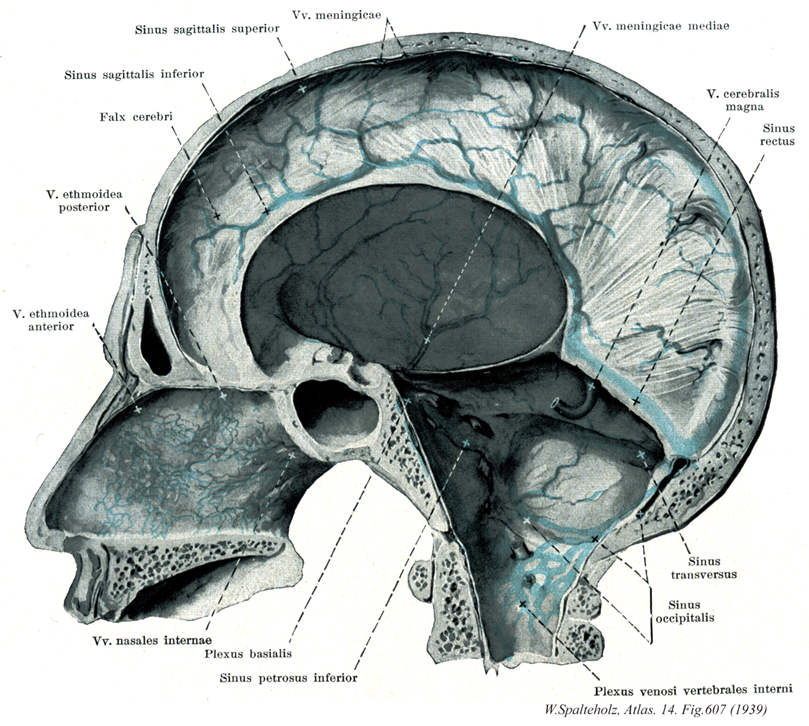

607

- 607_01【Meningeal veins硬膜静脈 Venae meningeae】 Small branches draining the dura mater.

- 607_02【Superior sagittal sinus上矢状静脈洞 Sinus sagittalis superior】 It lies within the root of the falx cerebri and extends from the crista galli to the confluence of sinuses.

- 607_03【Inferior sagittal sinus下矢状静脈洞 Sinus sagittalis inferior】 Small sinus at the free margin of the falx cerebri. It terminates in the straight sinus.

- 607_04【Falx cerebri; Cerebral falx大脳鎌 Falx cerebri】 Crescent-shaped portion of the dura mater projecting into the longitudinal cerebral fissure.

- 607_05【Posterior ethmoidal vein後篩骨静脈 Vena ethmoidalis posterior】

- 607_06【Anterior ethmoidal vein前篩骨静脈 Vena ethmoidalis anterior】

- 607_07【Internal nasal veins内鼻静脈 Venae nasales internae】

- 607_08【Basilar plexus; Basilar venous plexus脳底静脈叢 Plexus venosus basilaris; Plexus basilaris】 Venous plexus on the clivus that is connected with the cavernous and petrosal sinuses, as well as venous plexuses of the vertebral canal.

- 607_09【Inferior petrosal sinus下錐体静脈洞 Sinus petrosus inferior】 It runs from the cavernous sinus along the posterior inferior border of the petrous part of temporal bone to the jugular foramen.

- 607_10【Middle meningeal veins中硬膜静脈 Venae meningeae mediae】 Veins accompanying the middle meningeal artery.

- 607_11Galen, Vein of【Great cerebral vein大大脳静脈 Vena magna cerebri; Vena cerebri magna】 Short vein between the union of the two internal cerebral veins and the beginning of the straight sinus.

- 607_12【Straight sinus直静脈洞 Sinus rectus】 It commences at the union of the great cerebral vein and inferior sagittal sinus and runs within the root of the falx cerebri at its junction with the tentorium cerebelli to the confluence of sinuses.

- 607_13【Transverse sinus横静脈洞;横洞 Sinus transversus】 It commences at the confluence of sinuses and passes laterally to the sigmoid sinus.

- 607_14【Occipital sinus後頭静脈洞;後頭洞 Sinus occipitalis】 It commences with a venous plexus at the foramen magnum and passes within the root of the falx cerebelli to the confluence of sinuses.

- 607_15【Internal vertebral venous plexus内椎骨静脈叢 Plexus venosi vertebrales interni】